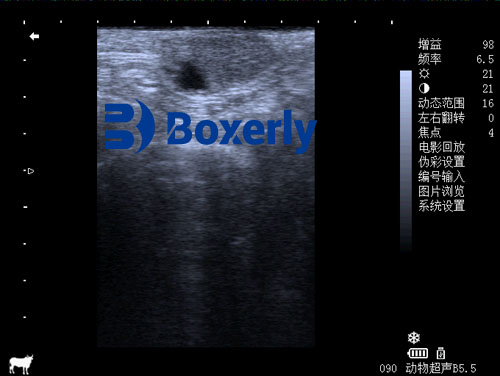

Ultrasonography has become a gold standard in veterinary reproductive imaging due to its non-invasive nature and ability to provide real-time visual feedback. With B-mode (brightness mode) imaging, veterinarians can view internal structures of the ovary and identify the corpus luteum based on its size, shape, and echogenicity.

Early detection: CL can be seen as early as 1 day after ovulation, appearing as a weak to moderate echoic structure.

Differentiation of CL types: Ultrasound helps distinguish between normal cyclic CL, persistent CL, and pregnancy CL based on echotexture and surrounding ovarian tissue.